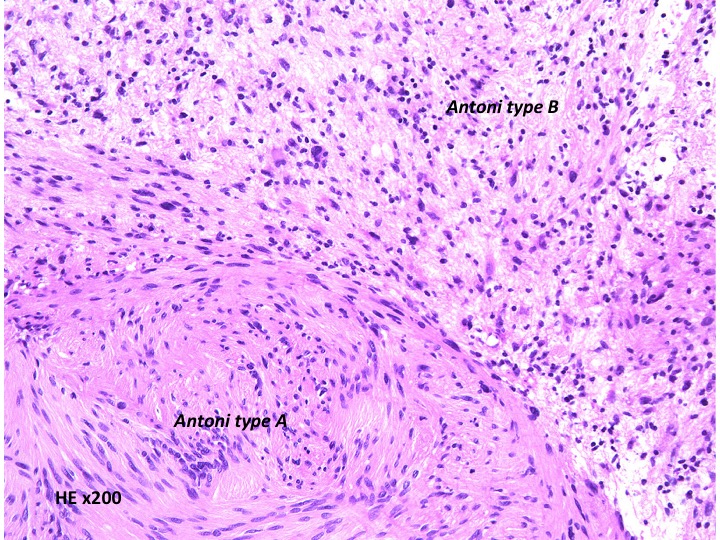

Antoni type A(密な部分)とAntoni type B(そな部分)の混在

紡錐型の核を有する腫瘍細胞で構成されます。左側の写真のように,古典的病理所見として,束状 fascicular に配列する密な組織である Antoni A Typeと網状 reticular で疎な組織である Antoni B Typeが混在するパターンを示します。神経鞘腫では多少の核の異型性がみられても悪性像とはいえません。嚢胞を形成したり,時には毛細血管拡張 simple hemangioma を思わせるような著明な血管の増生があり腫瘍内出血をきたすことがあります。